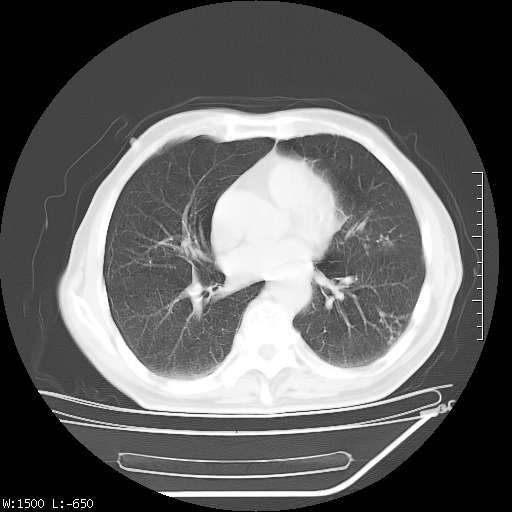

标题: CT23994:男、72、咳嗽、气短两月余,近来消瘦。 [打印本页]

标题: CT23994:男、72、咳嗽、气短两月余,近来消瘦。

tb可能性大(双肺均可见片状密度增高灶,其内可见低密度空洞)。

右上肺大片状密度增高影,与胸膜关系密切,内见低密度透亮影,胸膜下可见三角形不张影,左下肺沿支气管走形结节影,纵膈内淋巴结显示。考虑结核并疤痕性不张可能性大,建议穿刺活检,排除肺泡癌。